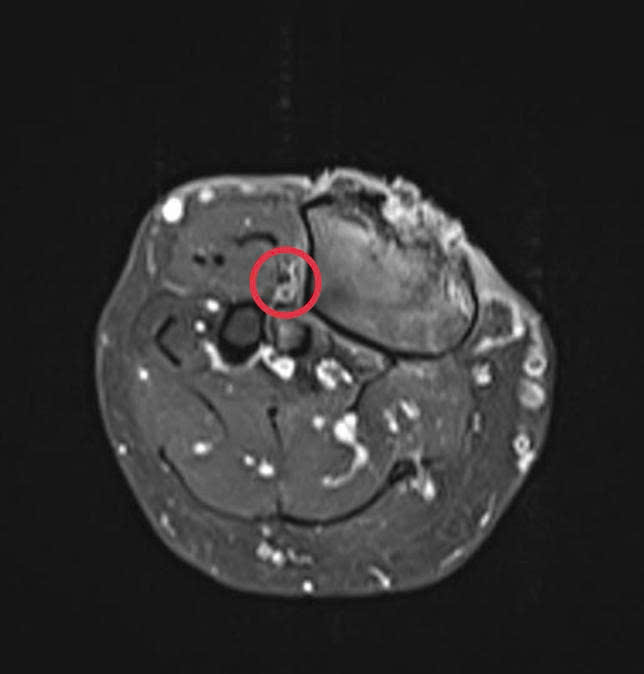

Hình 3: Phần tổn thương ung thư xâm lấn gần như toàn bộ chu vi xương chày về mặt cắt ngang, nhưng chưa xâm lấn bó mạch chày trước (phần khoanh tròn đỏ)